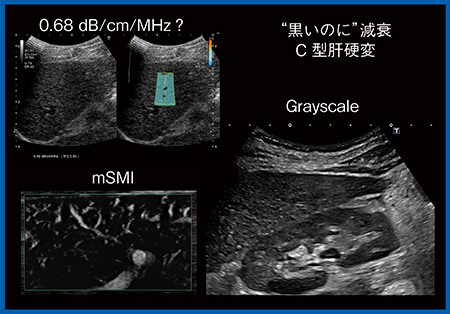

組織に反射した音波を受信して画像化する超音波診断装置では,受信できない場合には低エコーになる。一般的に超音波画像では黒い(低エコー)領域の後方は白くなるが,まれに黒い部分の奥も黒く表示される“矛盾する黒のパターン”を示すことがある。この現象は同じ低エコーでも,組織の構造が均一で散乱体に乏しい場合と,不整で後方散乱に乏しい場合で異なり,この組織構造の違いを鑑別するにはエコーの減衰の算出がポイントになる。減衰係数を求めることで,肝腎コントラスト(intensity ratio)だけではわからない,減衰を伴う組織性状の判断が可能になる。

図4は,黒い(低エコー)にもかかわらず後方エコーが減衰している症例である。グレイスケール上では肝腎コントラストがほぼ同一だが,減衰係数は高くなっている。SMIでは血管が不整に描出され,C型肝硬変とわかる。組織の構築が乱れ,散乱が強い場合には信号が戻ってこないため,Bモード画像では判断は難しい。減衰係数を利用することで“見えない波”をみることが可能になる。

図4 低エコー領域の後方が減衰する例(C型肝硬変)